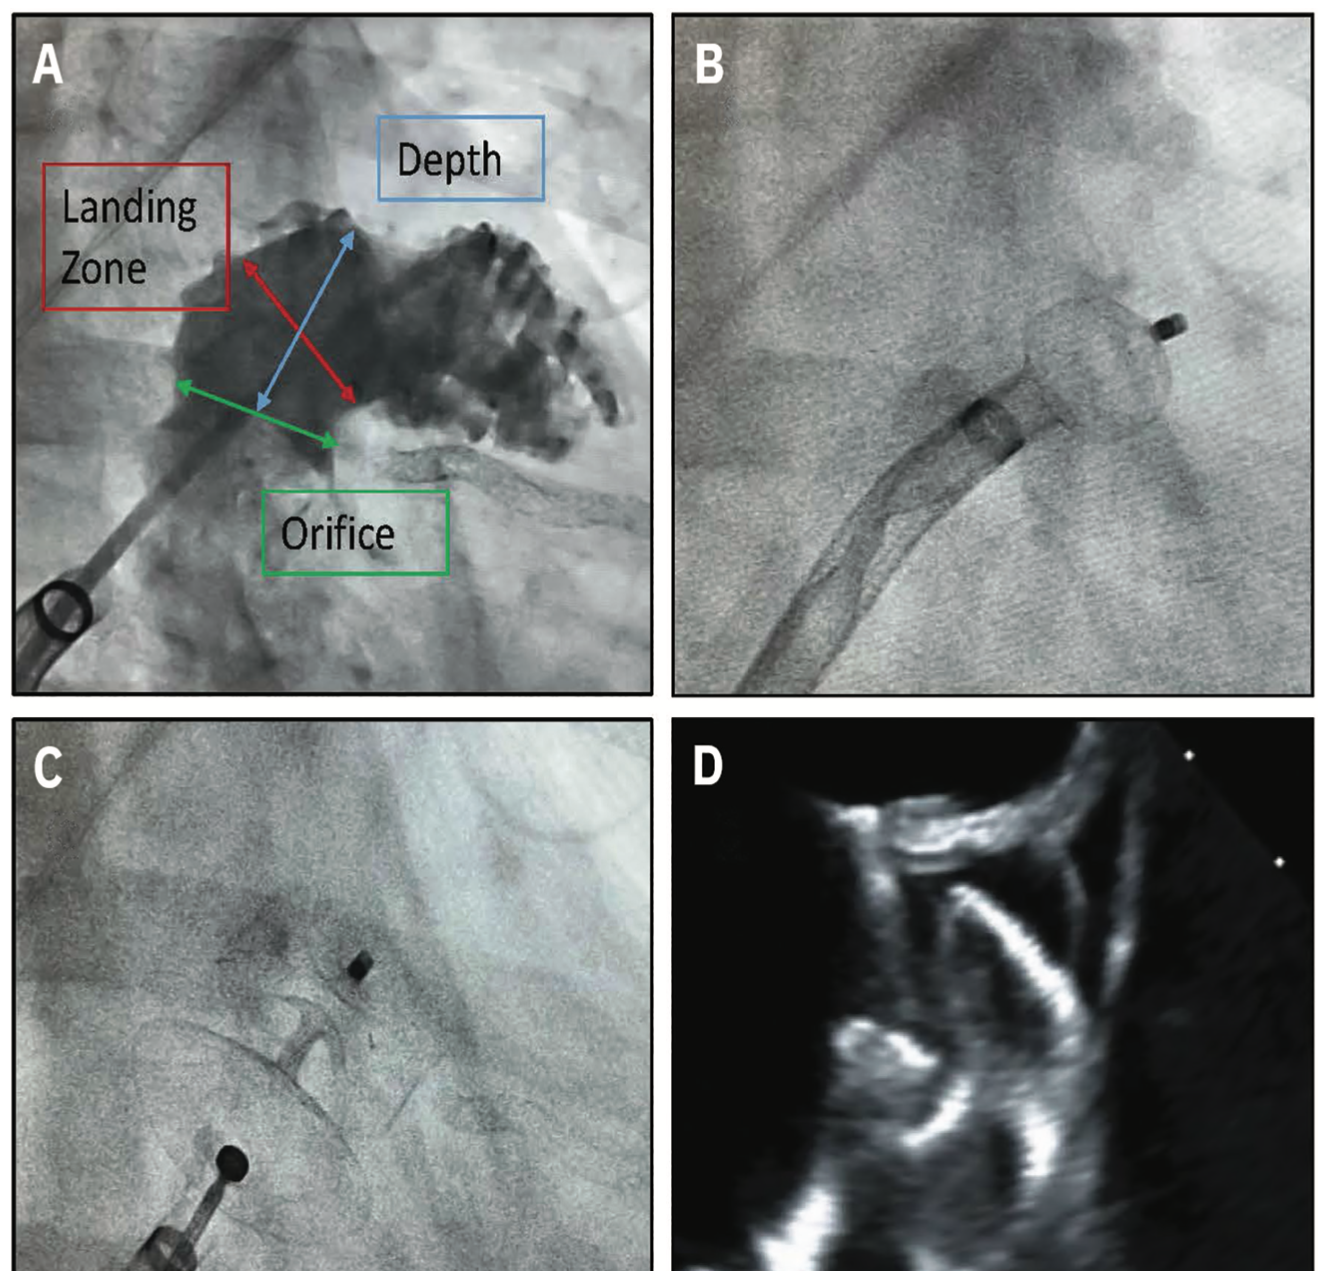

Advanced cardiac imaging is a foundation for any successful LAAC program. Institutions looking to start a LAAC should possess a strong and dedicated cardiac imaging program with TEE. The availability of dedicated anesthesia staff, an advanced imager, and TEE resources may limit the growth of some LAAC programs. Intracardiac echocardiography (ICE) imaging5 with conscious sedation may draw further interest to expand access to growing programs (Figure 5).

Video 2. ICE imaging of the LAA for Watchman deployment.5